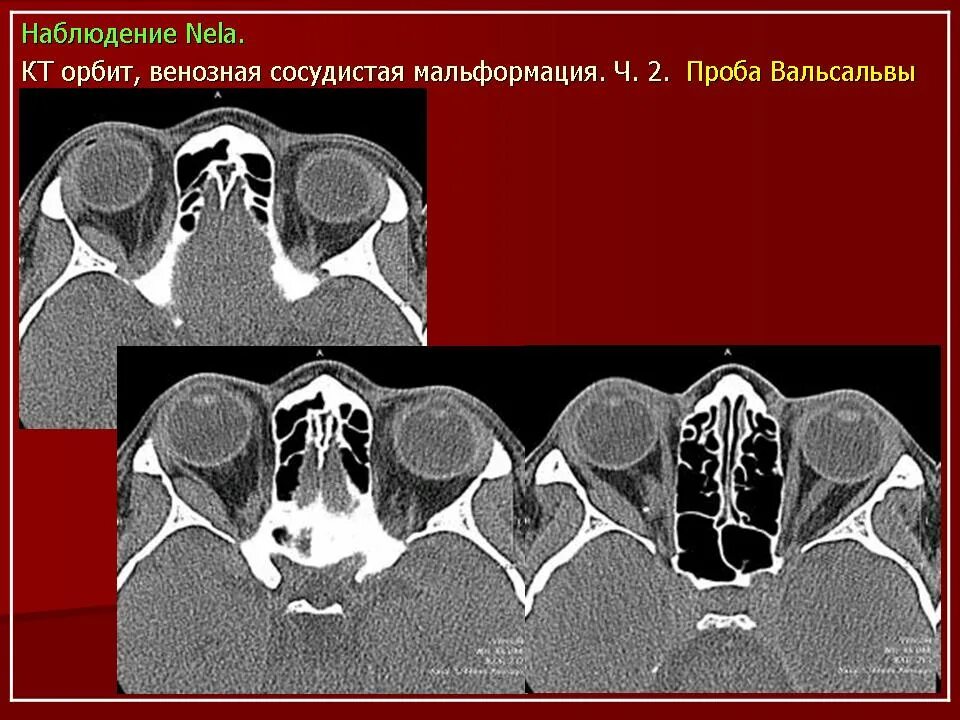

Данные кт